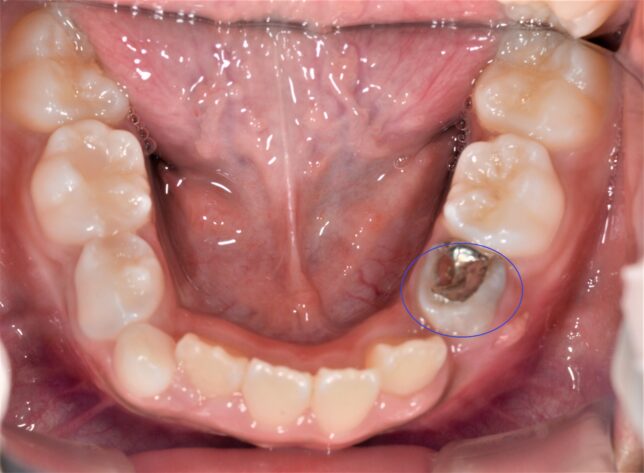

しかし、上下の永久歯の生えるタイミングだったり、遺伝的な顎の位置が原因で噛み合わせが反対(互い違い)になってしまうことがあります↓

これを歯科では

反対咬合

といいます。